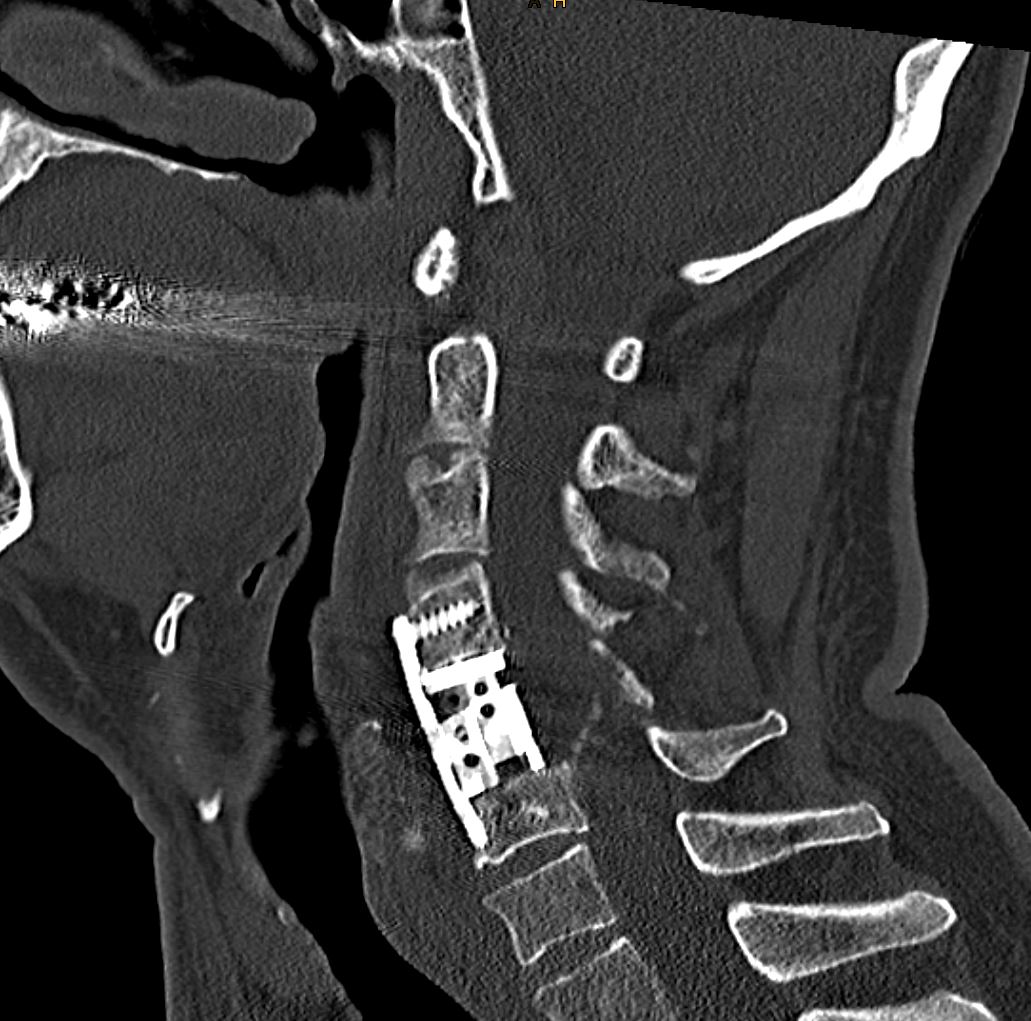

Παραγαγγλίωμα Α5 Σπονδύλου – Σωματεκτομή